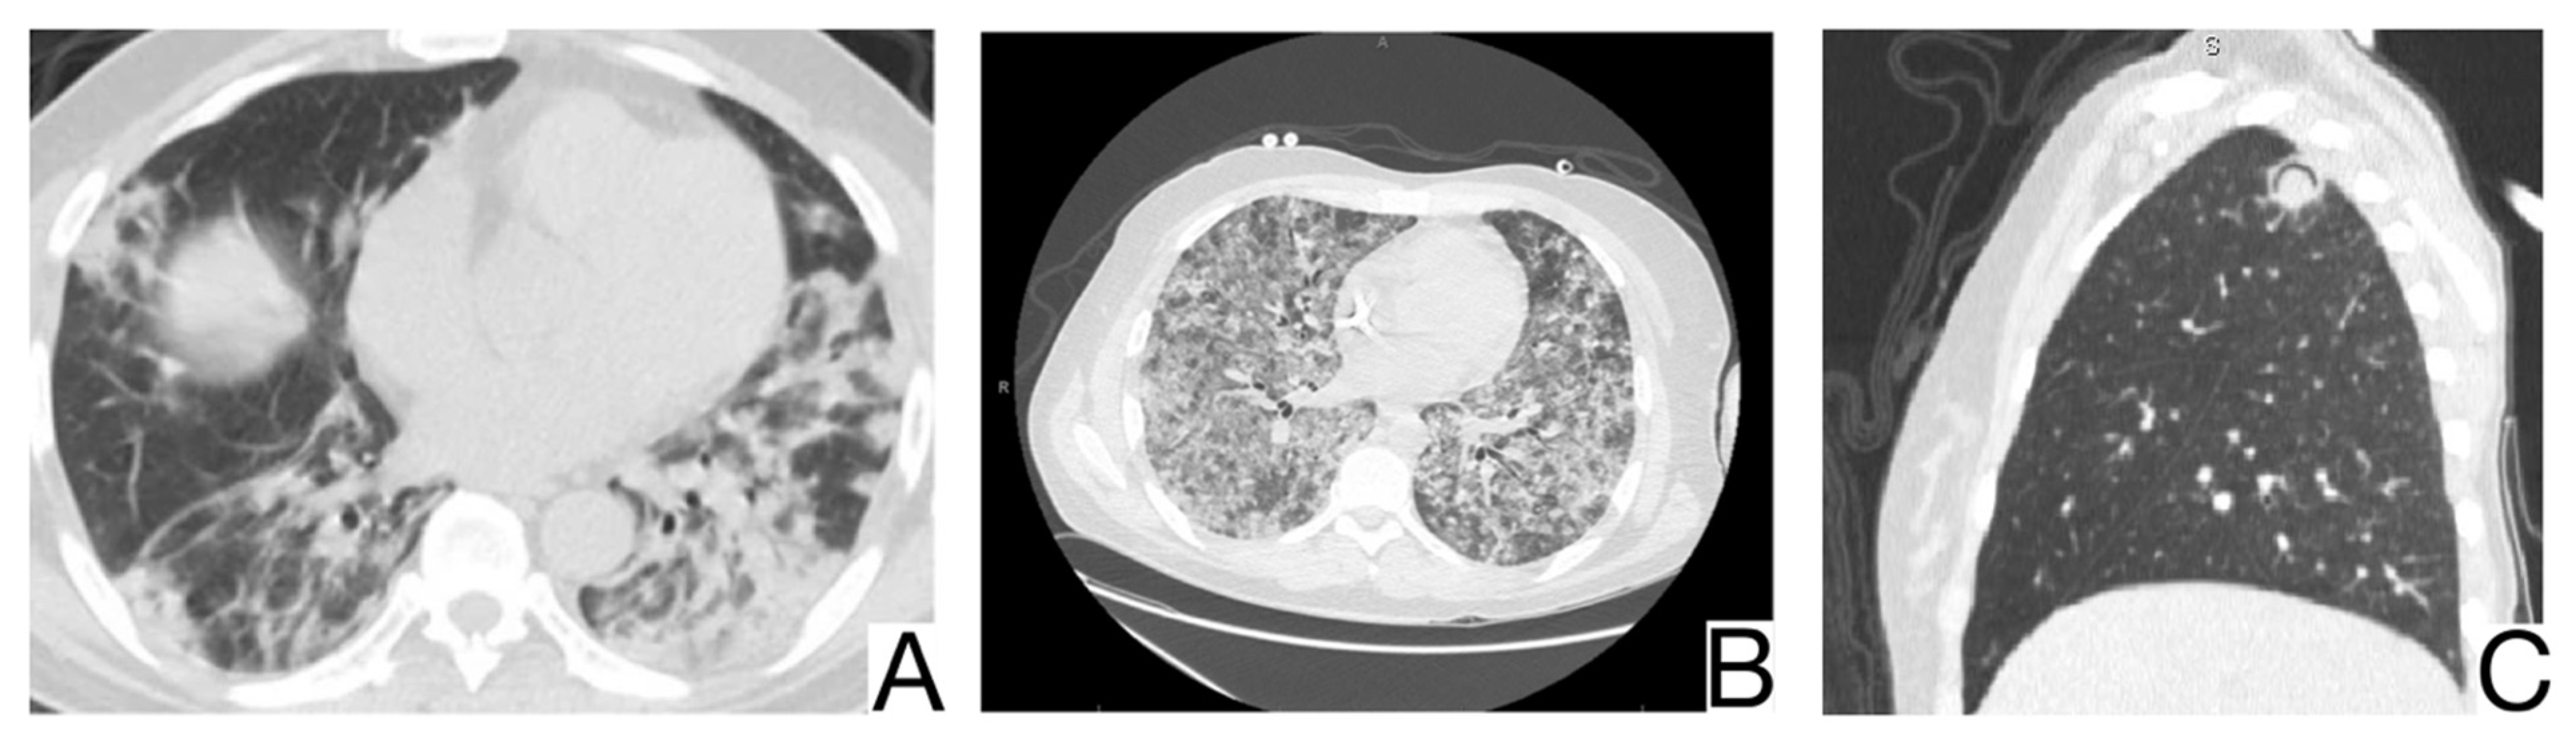

10.2. Viral Pneumonia

10.3. Pneumocystis Pneumonia